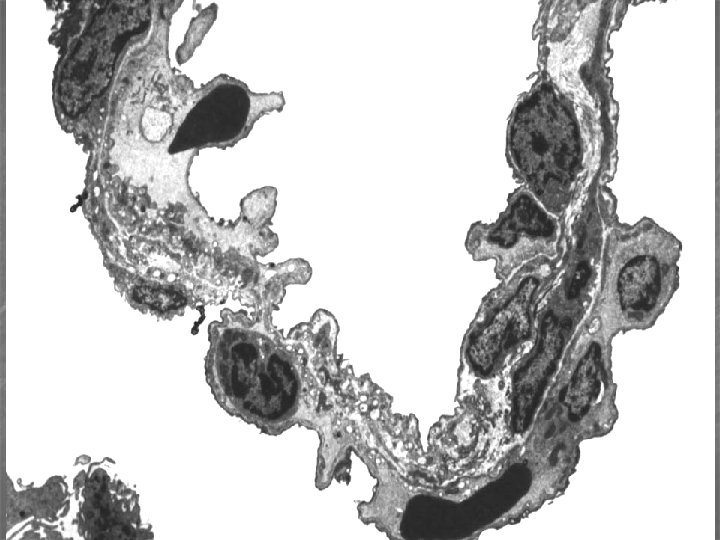

Plicní alveolus (300 – 500 mil. v každé plíci, plocha 70 – 80 m 2) n n n respirační epitel (2 typy pneumocytů: membranózní* - 97% plochy, výměna plynů, granulovaný** – 3% plochy, plicní surfaktant retikuloelastická membrána (vlákna, fibroblasty, amorfní substance) krevní kapiláry – souvislé Póry v interalveol. septu – kolat. cirkulace vzduchu alveolární makrofágy * alveolární buňky I, ** alveolární buňky II

Plicní surfaktant n na povrchu alveolárního epitelu snižuje povrchové napětí v alveolu a brání jeho kolapsu (atelektáze) při výdechu lipidy (90– 95%) a proteiny.

Krev-vzduch bariéra (šířka 0, 1 – 1, 5 μm) n n n surfaktant cytoplazma membranózního pneumocytu lamina basalis respiračního ep. lamina basalis endotelu kapiláry cytoplazma endotelové buňky

Respirační epitel a bariera vzduch-krev lumen kapiláry s erytrocyty Vazivo Membranózní pneumocyt Granulózní pneumocyt